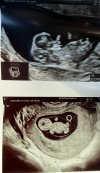

Hejka:) wczorajsza wizyta mnie bardzo uspokoiła wszystko jest ok:) potem byłam

na prenatalnych i teraz czekam z niecierpliwością na wyniki i usg prenatalne☺️ A dzisiaj dostałam takiego powera, że nagotowałam, psie fryzury ogarnęłam i polatałam po lesie 10 km jak przed ciążą bez zadyszki🥰

Załączniki

• IMG_0906.jpeg

IMG_0906.jpeg

1,5 MB · Wyświetleń: 51